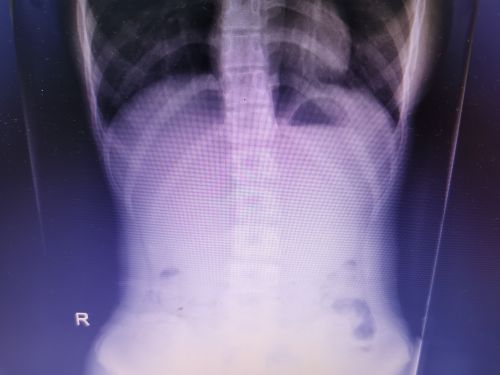

入院时的腹部x片可以看到,肠子里有3枚圆形异物。

腹部X光检查发现,小可的右下腹有3枚圆形异物,张先华主任医师和龙毅副主任医师仔细为小可进行体查,耐心询问病史,结合CT结果,确诊为肠道异物。由于异物系3枚纽扣电池,一次性取出十分困难,发生肠梗阻、肠粘膜损害导致肠穿孔的风险大;考虑到电池已经进入结肠,自行排出的可能性大,于是决定给予保守治疗,每天监测腹部X片,进食粗纤维饮食,同时服用乳果糖促排便。三天后,3枚纽扣电池随大便排出,家长悬着的心终于放下。